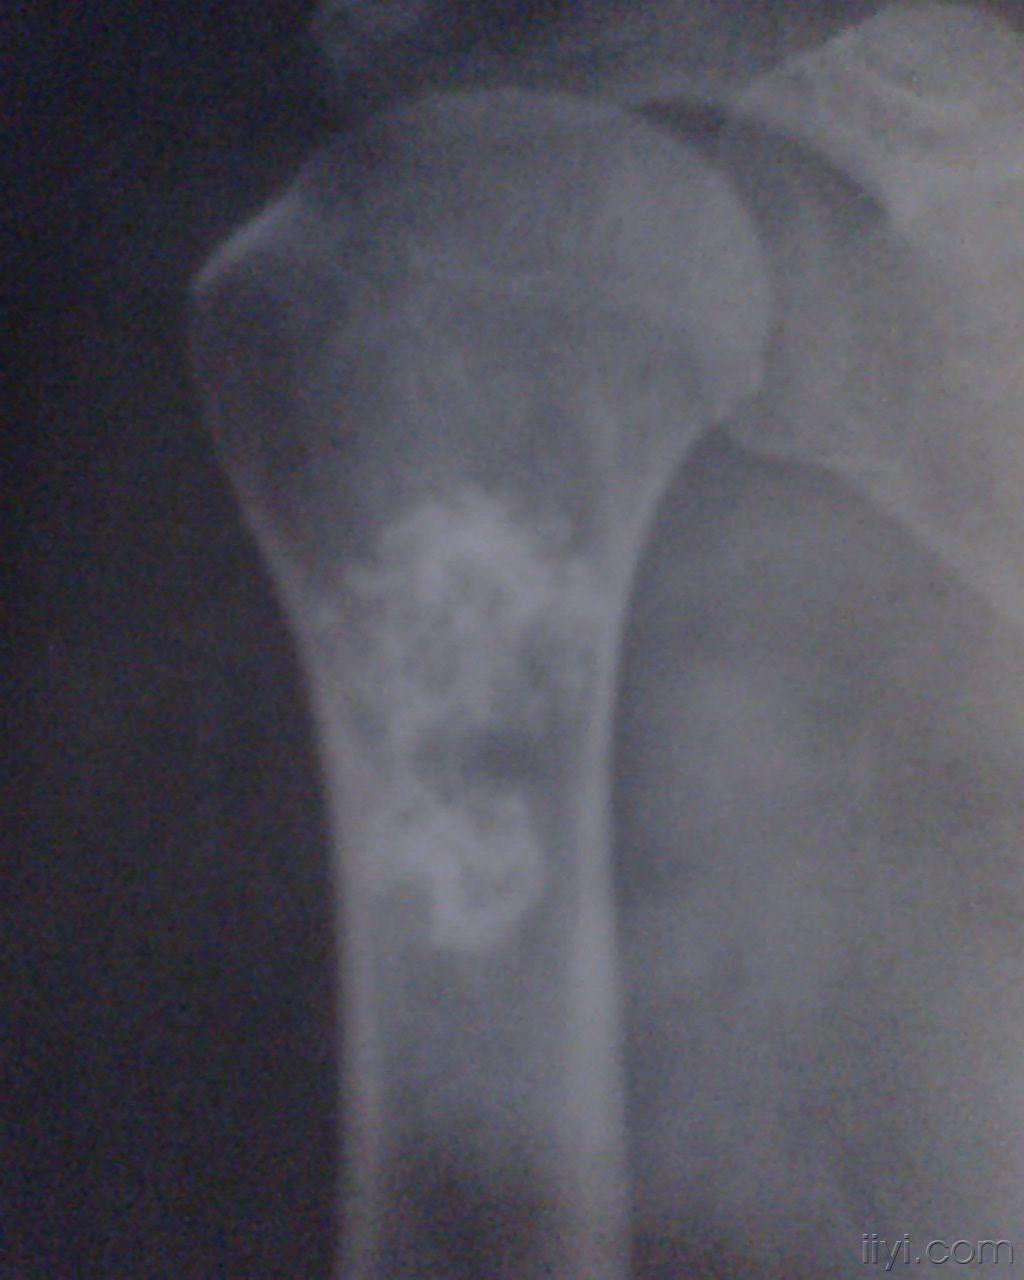

骨梗死的x片,比较少见哦

图片尺寸2576x1932